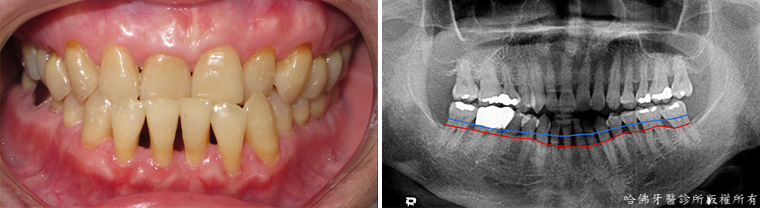

臨床上最多見的因牙周病而牙齒不正常移動案例,是上顎門齒漸漸外移。(圖6)。

(圖6)臨床上最多見的因牙周病造成牙齒不正常移動案例,使上顎門齒漸漸外移。